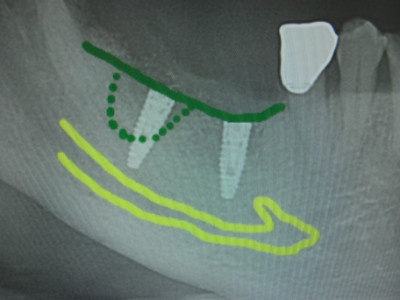

今日は右下6,7番相当部にスプリットクレストして骨幅を押し広げての埋入でした。

6歯槽頂部で骨幅が4ミリしかないケースでした、7,8番部は4か月ほど前に抜歯ソケットプリザベーションして骨造成を施術しております。